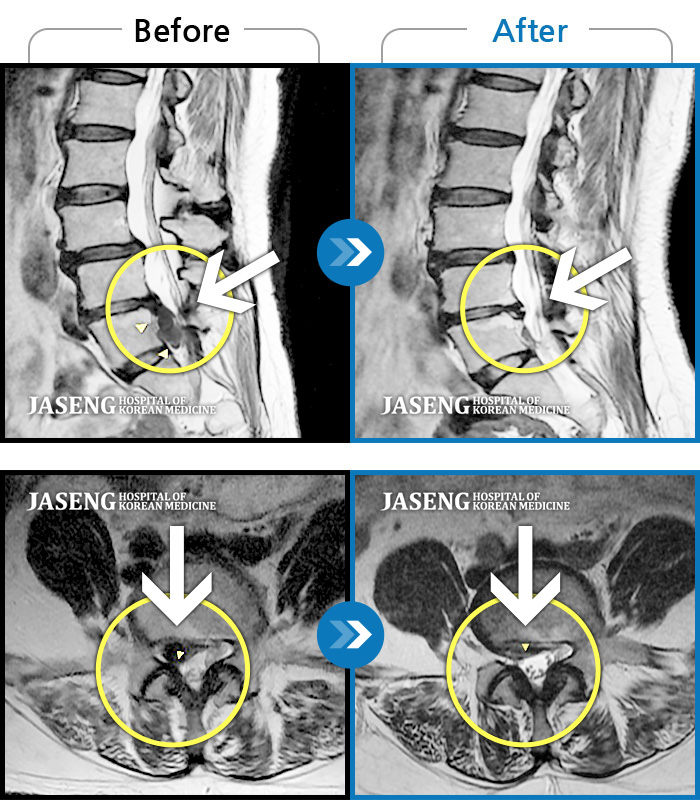

허리디스크

해운대 · 이상건 원장

허리통증, 좌측 다리 저림 및 근력 저하

촬영시기

2017.09.08 ~ 2018.05.11